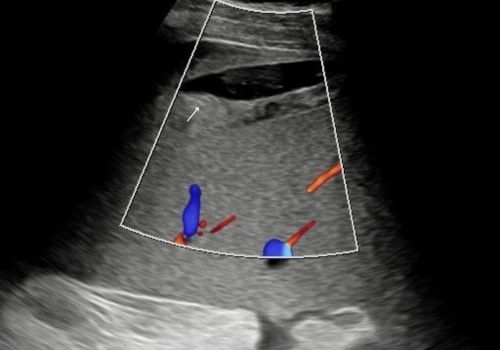

A heterogenous area with a small area of central fluid left subphrenic space surrounding/indistinct from the superior spleen was identified with no colour doppler flow.

Figure 5 and 6 above; Heterogeneous area adjacent to the spleen with fluid demonstrates no colour doppler flow (arrow).